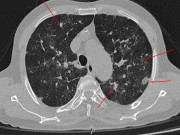

TS.BS Đào Hữu Nam - Trưởng khoa Điều trị tích cực, Trung tâm Hồi sức tích cực người bệnh COVID-19 trẻ em, Bệnh viện Nhi Trung ương cho biết, đây là một trong số những bệnh nhân nguy kịch nhất tại trung tâm, khi nhập viện trẻ trong tình trạng sốt cao và mệt mỏi, khó thở, suy hô hấp - tuần hoàn. Được biết, tiền sử cháu khỏe mạnh bình thường, không có bệnh nền hay biểu hiện gì đặc biệt.

Theo bác sĩ Nam, thời điểm đó, các bác sĩ đã nghĩ tới nhiều tình huống như, có thể do cháu đã có đợt nhiễm SARS-CoV-2 trước đó, nên tình trạng sốc, tổn thương cơ tim nặng có thể là trong bệnh cảnh của hội chứng viêm đa hệ thống (MIS-C). Nhưng cũng có thể do một đợt nhiễm virus cấp tính khác gây ra.

Do đó, cùng với các biện pháp hồi sức ban đầu, hỗ trợ chức năng sống cho cháu, các bác sĩ đã phải thăm dò thêm các xét nghiệm để xác định chẩn đoán chính xác căn nguyên và có các giải pháp điều trị thích hợp.

Trước tình trạng nguy kịch của trẻ, các bác sĩ đã tiến hành phối hợp nhiều biện pháp như thở máy, lọc máu bằng quả lọc hấp phụ. Trong 1-2 ngày đầu, bệnh nhân khá ổn định và tiên lượng tốt lên, nhưng sau đó bệnh nhân lại bất ngờ diễn biến nặng hơn, các bác sĩ đã quyết định cho bệnh nhi chạy ECMO với hy vọng sẽ giữ lại sự sống cho bé. Kết hợp tất cả các biện pháp điều trị, trải qua nhiều ngày căng thẳng, cuối cùng bệnh nhi cũng vượt qua giai đoạn nguy kịch, vượt qua lằn ranh mong manh của sự sống.

Bác sĩ Nam cho biết, tổng số ngày cháu Q được lọc máu là 5 ngày, thở máy trong 15 ngày và ECMO 8 ngày, sau giai đoạn nguy hiểm đó, bệnh nhân đã được cai ECMO và tập thở bình thường trở lại. Hiện các bác sĩ đánh giá tình trạng của bệnh nhi đã khá ổn định, khả năng hồi phục tương đối tốt, chức năng tim đã cải thiện rõ và chuẩn bị được xuất viện.